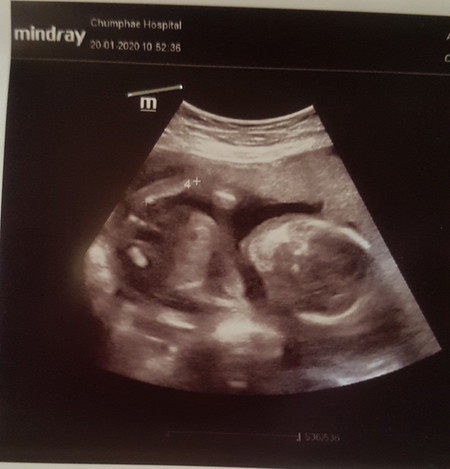

ใครพอดูเปนบ้างค่ะ หมอไม่ได้บอกเลยหญิงรึชายรูปตอนครรภ์ได้4เดือน

สอบถามค่ะว่ารูปนี้เป็นหญิงรึชายค่ะ

ชาย